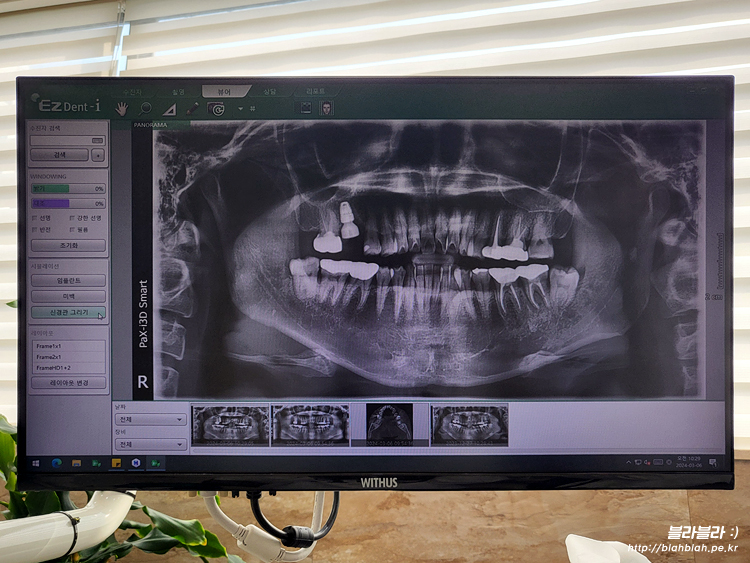

임플란트 동의서 작성하고 파노라마 CT 촬영 후

마지막으로 다시 파노라마 촬영하고